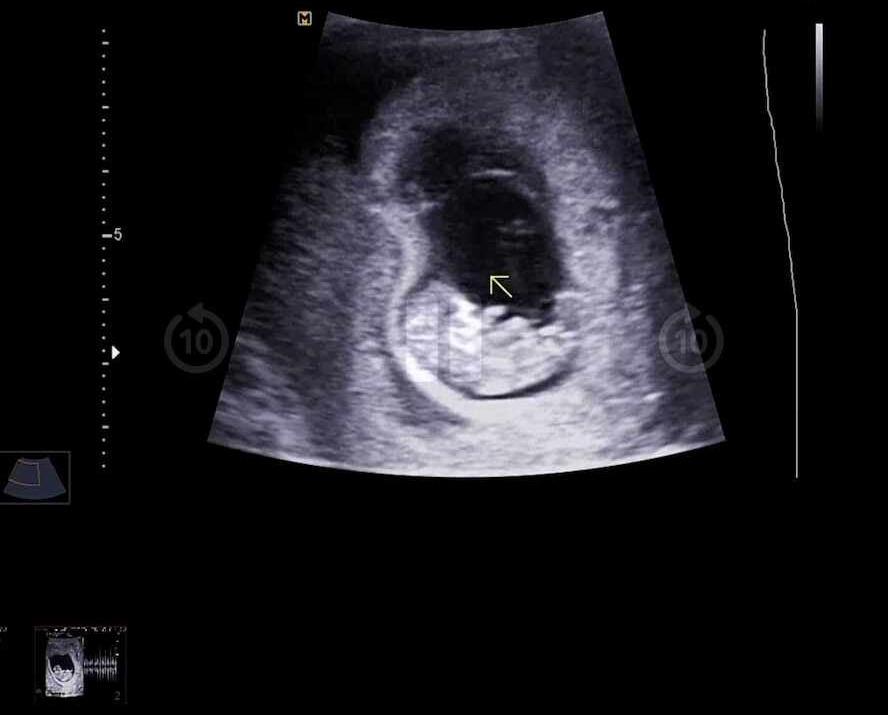

남편과 함께 간 산부인과에서 초음파를 보는데 어느덧 2.5센티로 자란 귀여운 튼튼이에게 팔다리가 다 있었다!

꼬물꼬물 움직이는 모습을 보니 정말 내 안에 생명이 있는 것이 실감이 났다.

8b8f8343-ccf7-11ed-9c6c-b4055da54885_01.jpg